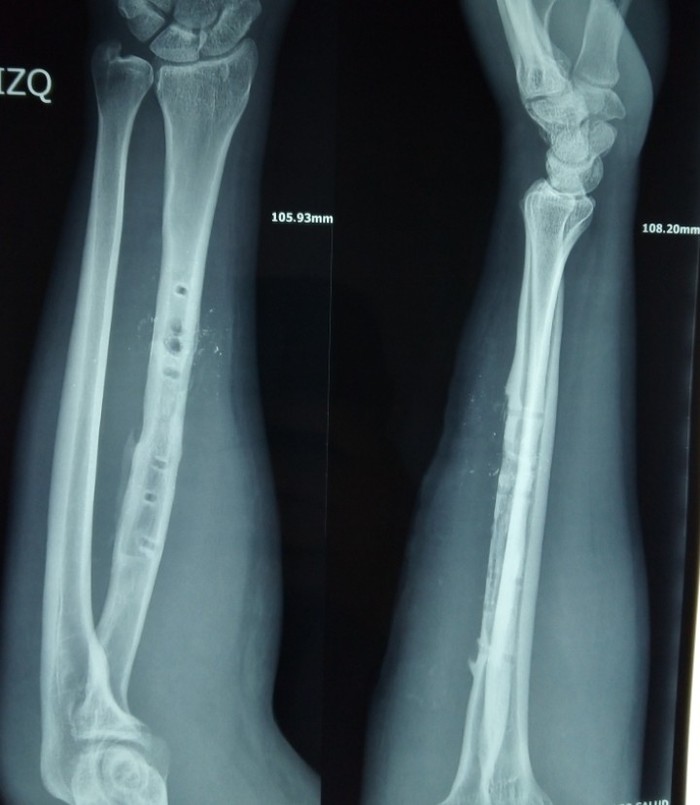

Сижу в частной поликлинике в Южной Америке. Приходит пациент, хочет удалить пластину из предплечья, которая 20 лет простояла.

Разрезали, вывинтили 5 винтиков из 6, а один- не вывинчивается.

Там винты, стандартно, под гексагональную отвертку.

Один винт, закрученный косо, не вывинчивается, головка повреждена, то есть гексагональная отвертка прокручивается. Вот этот винт:

Экстрактор не помог. Я сделал дреммелем прорезь в головке и пытались выкрутить обычной прямой отверткой. Не получилось.

Как обычно, костными кусачками тоже пытылись выкрутить.

Промучились 2 часа, у анестезиолога и ассистента закончилось время доступности.

Зашили рану, операция закончилась. Удалено только 5 винтиков, пшик, во влип.

Говорю: пластину удалим, но с винтом этим могут быть проблемы, при его удалении можно сломать кость, лучше его оставить, он внутри кости, беспокоить не будет.

Через дней 5, в клинике стали разрушать дальше винт: дреммелем, сверлом по металлу- разрушили головку полностью, пластину выбили.

Винт остался без головки, полностью в кости, зацепиться некак.

Стал делать сверлом углубление возле винта, ямку, но кость тонкая, можно и разрушить. В итоге сделали 2 канала выше и ниже винта, расшатали (молотком долбали в стороны каналов) и винт поддался.

Вывод для себя такой: удаление металла, который не сам ставил- только в клинике и стоить должно также как остеосинтез.